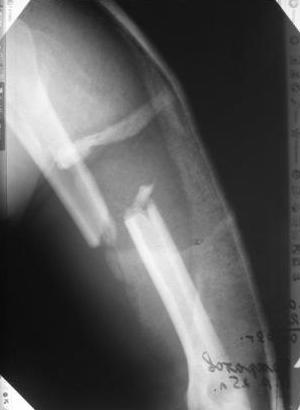

Re: Перелом н\3 плечевой кости. Тактика лечения?

У Синтеза (да и у других производителей, вероятно) есть блокируемые метадиафизарные пластины. Как раз для таких случаев. Учитывая высокую вероятность появления гетеротопических оссификатов на фоне ОЧМТ, успех во многом будет определяться стабильной фиксацией, санацией посттравматической гематомы, профилактикой послеоперационной гематомы (адекватный дренаж, эластичное бинтование), ранней разработкой движений.

Да, как раз блокированная пластина и стоит, не синтезовская метадиафизарная, Рыбинская, но на порядок дешевле, а профилактика всех осложнений - в данном конкретном случае, начало ранней на вторые сутки - после удаления дренажа разработки движений в смежных суставах. Если же идти с ревизией т.е. всё равно, открыто как вариант небольших разрезов при поперечном переломе можно и комбинированный мос (см.на вкладыше), хотя думаю для такого способа перелом всётаки низковат.

Спасибо Алексей! Я и планировал провести антеградное штифтование но меня смущал относительно небольшой дистальный отломок. Может для кого-то данные вопросы и кажутся пустяком...но я только недавно начал использовать в своей работе штифты преимущественно Synthes. Еще раз спасибо

Всё правильно, просто я несколько разрозненно пытался сказать на частных примерах, то , что Вы систематизировали. Совершенно верно данный перелом можно и так и эдак, наиболее оптимально антеградное штифтование, хотя я бы предпочёл пластину LCP(просто - ну лучше у меня это получается и всё, а больному не вредит тот же функциональный способ). А низковато для неблокированного штифтования с конструкциями с термомеханической памятью, то, что представленно на втором снимке.